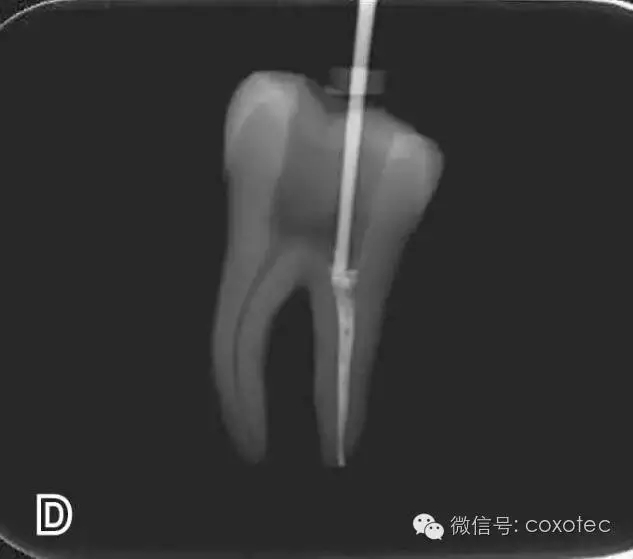

選擇非標(biāo)準(zhǔn)牙膠尖(如0.04、0.06 錐度牙膠尖)作為主尖,型號一般與根管預(yù)備最大號的器械型號一致,能到達(dá)距根尖0.5~1 mm 處,主尖尖段與根管壁緊密接觸。拍試尖X 線片進(jìn)行確認(rèn)(圖3)。

圖3 試尖,A.試主尖 B.拍試尖X片